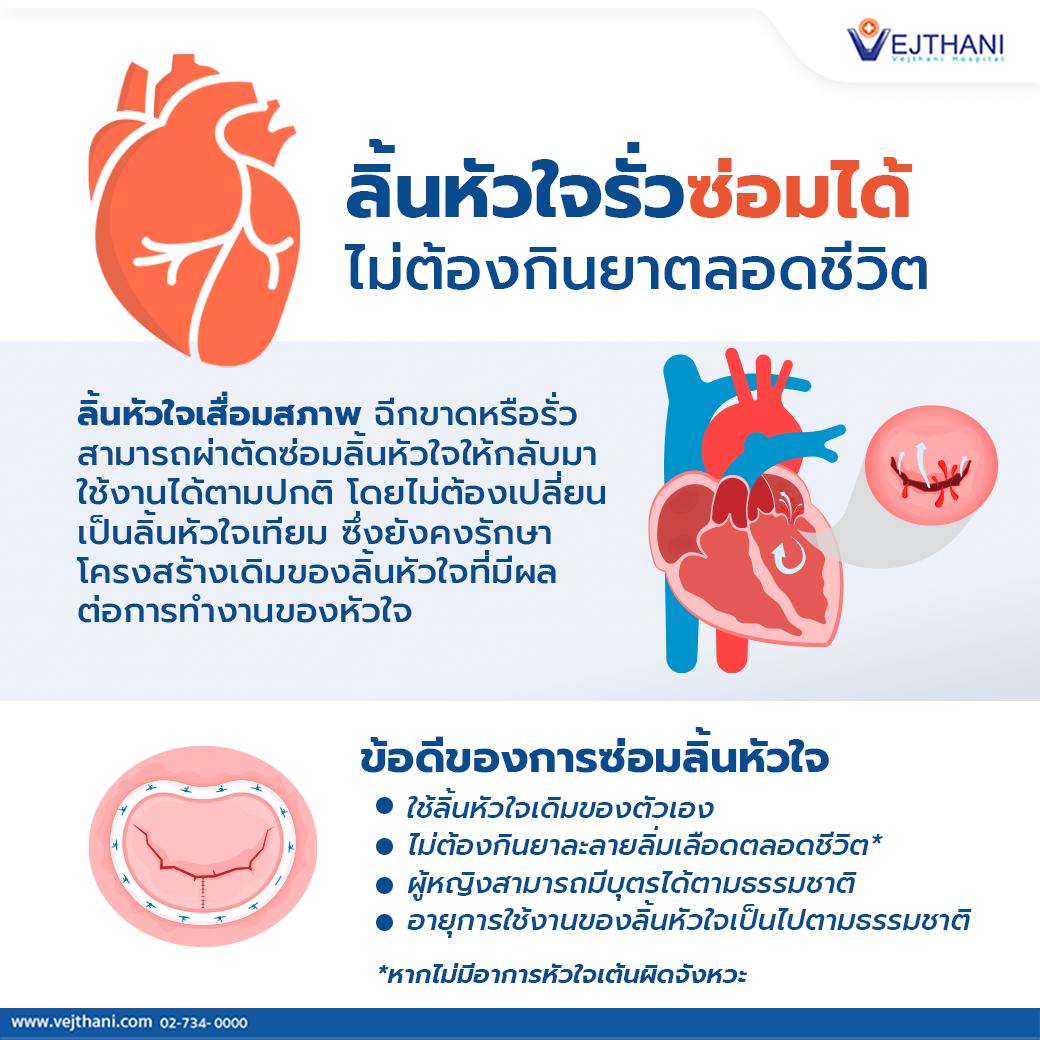

เอ็มอาร์ไอและเอกซเรย์คอมพิวเตอร์หัวใจในผู้ป่วยโรคหัวใจแต่กำเนิด … บทความเกี่ยวกับ โรคลิ้นหัวใจรั่ว

บทความเกี่ยวกับ โรคลิ้นหัวใจรั่ว โรคหัวใจ – โรงพยาบาลรวมแพทย์ฉะเชิงเทรา

ตกแต่งหัวใจ, ภาพตัดปะหัวใจ, หัวใจสีแดง, หัวใจคู่สีแดงภาพ PNG และ PSD … โรคลิ้นหัวใจ – โรงพยาบาลเวชธานี

โรคลิ้นหัวใจ – โรงพยาบาลเวชธานี 15+2 ภาพเอกซเรย์ที่ใช้หาสิ่งแปลกปลอมในร่างกาย แต่กลายเป็นตัวภาพนั่นล่ะ …